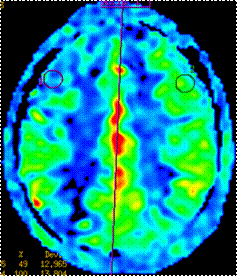

颅脑MRI提示:双侧基底节、放射冠区多发腔隙性脑梗死(如图一);颈部血管彩超提示:双侧颈动脉重度狭窄。3D-ASL提示:右侧额叶局部灌注减低,感兴趣区CBF测值为(28.39±12.97)mL/100g/min,低于对侧镜像感兴趣区测值(57.15±13.80)mL/100g/min(如图二)。DSA示:1、双侧颈内动脉起始部重度狭窄,狭窄程度均约90%,右侧狭窄长度约8mm(如图三);2、左侧颈总动脉末端中度狭窄,狭窄程度约50%,狭窄长度约1.0cm(如图四)。

图二